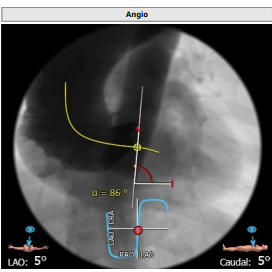

第一枪造影

跨瓣

Nmued20预扩1

Nmued20预扩2

最后一枪造影